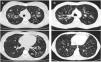

CT images comparison between male and female with the same FEV1: (A) 35 year-old female. Severe bronchiectasis on upper lobes (scored 3), mild peribronchial thickening (scored 1), peripheral mucus plugs are present on upper lobes (scored 2), sacculations are present on left lower lobe. Sparing of distal peripheral zones is detected. Total Bhalla score: 10. FEV1 60%. (B) 40 year-old male. Moderate bronchiectasis (scored 2), mild peribronchial thickening (scored 1), mucus plugging (scored 2) was present on upper lobes. Sparing of distal peripheral zones is detected. Total Bhalla score: 17. FEV1 60%.